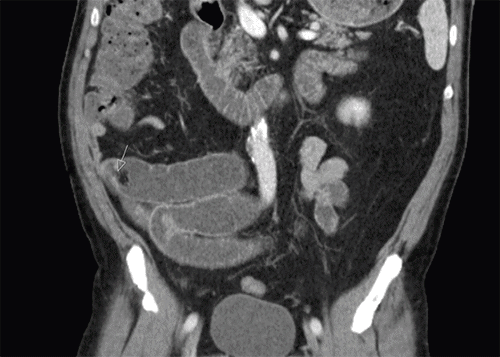

Four months after that discharge, he again presented for nausea and diffuse abdominal pain. At this visit, CT of the abdomen and pelvis showed mid and distal small bowel distention with air-fluid levels and a transition zone in the right lower quadrant (Figure 1). Due to the previous failure of medical management, it was decided to proceed to the operating room for surgical management. Diagnostic laparoscopy demonstrated an omental adhesion attached to the anterior abdominal wall near the umbilicus. The small bowel mesentery appeared to swirl around this adhesion, causing a mechanical obstruction. Adhesiolysis was performed, and the bowel was laparoscopically inspected in its entirety from the cecum to the duodenum. No other evidence of injury or pathology was noted. The patient's postoperative course was unremarkable, with good return of bowel function.

Figure 1. Coronal CT scan. Published with Permission

Transition point at arrow in the left lower quadrant. This finding would subsequently lead to laparoscopy.